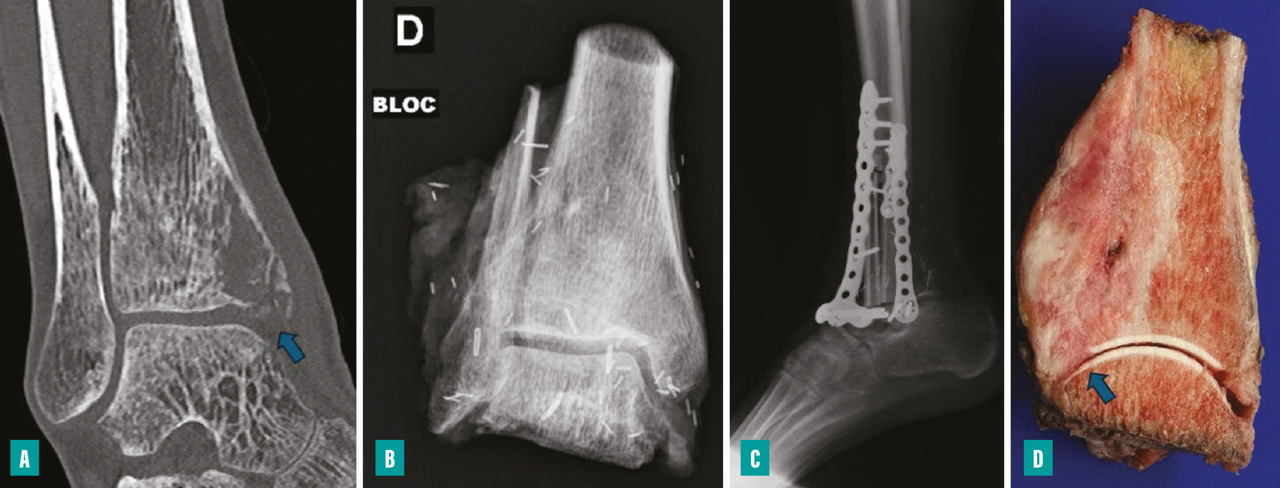

Pour les sarcomes des membres, la préservation de la fonction articulaire est le facteur déterminant. Dans la mesure du possible, les chirurgies avec préservation épiphysaire doivent être privilégiées (fig. 1). En cas d’atteinte épiphysaire, le choix de la technique opératoire dépend de la présence ou non d’un envahissement intra-articulaire, qui nécessite alors de recourir à une résection dite «  extra-articulaire  », techniquement plus exigeante (fig. 2). L’imagerie par résonance magnétique (IRM) a une place de choix pour identifier cette contamination articulaire.

La survenue d’une fracture pathologique rend plus difficile l’obtention de marges saines du fait de la dissémination de l’hématome dans les tissus mous. Elle ne semble pas augmenter le risque de récidive locale – à la condition d’obtenir des marges saines – et ne constitue donc pas une indication d’amputation (fig. 3). Lorsqu’elle survient en cours de traitement, elle fait craindre une mauvaise réponse à la chimiothérapie, qui pourrait expliquer le moins bon pronostic de ces patients.3,4